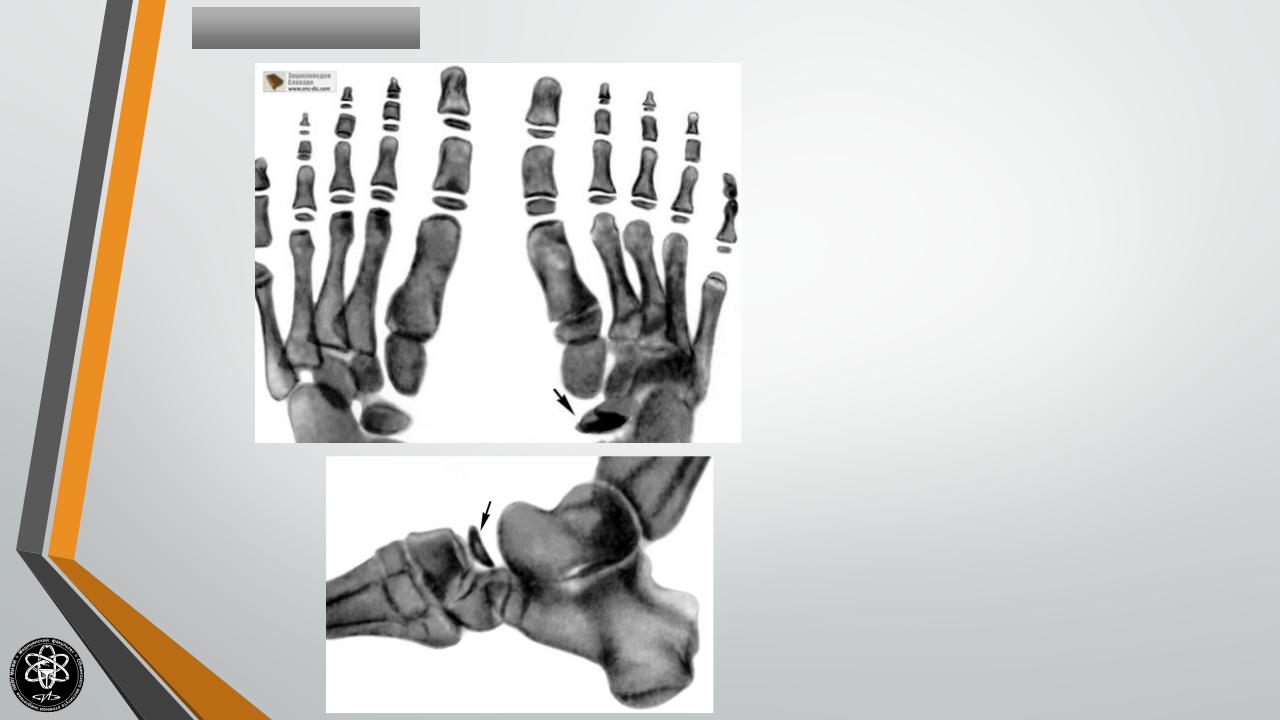

БолезньКелера-II

Остеохондропатия

головок

II или III

плюсневых костей.

Чаще поражает девочек, развивается в

возрасте 10-15 лет. Болезнь Келера II

начинается постепенно. В области поражения

возникают периодические боли, развивается

хромота, проходящая при исчезновении

болей.

При

осмотре

выявляется

незначительный отек, иногда – гиперемия

кожи на тыле стопы. В последующем

развивается укорочение II или III пальца,

сопровождающееся

резким

ограничением

движений. Пальпация и осевая нагрузка резко

болезненны.

Заболевание не представляет значительной угрозы для последующего нарушения функции конечности. Показано амбулаторное лечение с максимальной разгрузкой пораженного отдела стопы. Пациентам иногда накладывают специальный гипсовый сапожок, назначают витамины и физиотерапию.